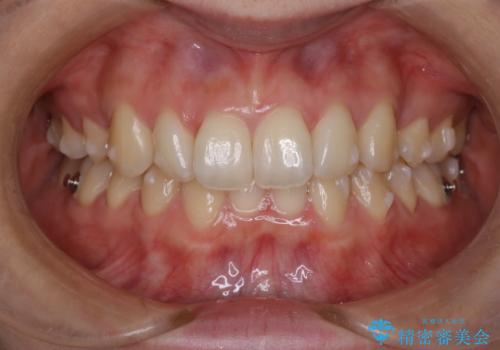

抜歯矯正×インビザライン|上下のバランスを整え、美しい歯並びへ

- 患者様は、上下の噛み合わせのバランスが悪く、特に上顎の前歯の突出を気にされて来院されました。診査の結果、下顎の歯並びに合わせて上顎を後方へ移動させる必要があると判断し、上顎の小臼歯2本を抜歯することを提案しました。目立たない矯正を希望されたため、**インビザライン(マウスピース矯正)**を選択。計画的にスペースを作りながら、バランスの取れた歯並びを目指しました。

治療はまず、上顎の小臼歯を2本抜歯し、そのスペースを利用して前歯を後方へ移動させました。インビザラインはアタッチメントを併用し、より効率的に歯を動かせるよう調整。定期的なチェックとアライナーの交換を続け、約3年かけて理想的な歯並びと噛み合わせを実現しました。治療後はリテーナーを使用し、安定した状態を維持。患者様からは「口元がスッキリし、横顔の印象も変わった」と嬉しいお声をいただきました。